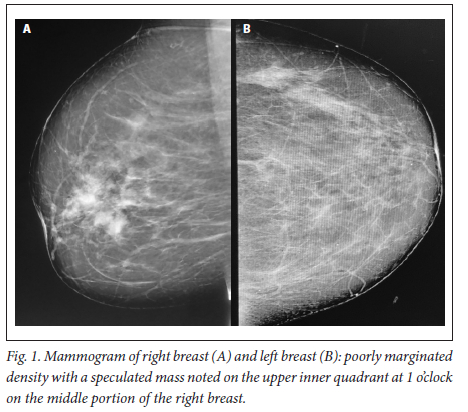

A 39-year-old obese woman had had a lump in the right breast for 18 months. She had gone to her local hospital when she noticed the lesion. A core biopsy was done and she was referred to the breast oncology clinic at Mankweng Hospital in Polokwane, Limpopo Province, South Africa, for further assessment and management. She had previously been healthy, with no known comorbidities and no family history of malignancy. On enquiry about her gynaecological history, she stated that her menarche had been at age 12, and she was still having normal periods and on contraception. She had a 15-year-old child, born when she was 24. After the birth of this child she had two more pregnancies, both resulting in unexplained stillbirths at term. She had no history of pregnancy-induced hypertension or any medical conditions diagnosed during pregnancy. After her discovery of the breast lump she was diagnosed with young-onset hypertension. There were no associated weight changes, and she was HIV negative. On examination she had a scar on the right upper quadrant, no palpable axillary lymph nodes, an elevated blood pressure (150/93 mmHg, pulse rate 88 bpm) and a high body mass index (37.7 kg/m2). The rest of the vital signs and the findings on systemic examination were unremarkable. On examination of the breast, the tumour was clinically staged as T3N0M0, making it stage IIB. Histological evaluation showed nests of cells infiltrating extensively throughout the tissue. The cells were hormone receptor (oestrogen and progesterone) positive, the HER2 score was 3+ and the Ki-67 proliferation index was 50 - 60%. Synaptophysin (SYP) and chromogranin (CGA) cytoplasmic staining was positive within the tumour cells, features in keeping with grade 3 invasive carcinoma showing neuroendocrine differentiation. A mammogram (Fig. 1) revealed poorly marginated density with a speculated mass noted on the upper inner quadrant at 1 o'clock on the middle portion of the right breast. The mass expended anteriorly to the retro-areolar space causing minimal traction of the peri-areolar skin and nipple. There were associated architectural distortions and trabecular thickening. The retromammary space was grossly normal bilaterally. There was no thickening of overlying skin, and no dilated ducts bilaterally. Regional benign calcifications were noted in the left breast. No axillary lymph nodes were visualised bilaterally. For further evaluation, a computed tomography (CT) scan (Figs 2, 3 and 4) was done and revealed multiple enlarged lymph nodes in the right axillary region. The right breast was ill defined with trabecular thickening and nipple retraction. The breast mass did not extend into the retromammary space, and the pectoralis muscle was grossly normal. Hypodense areas were noted in the thoracic and lumbar vertebrae, with involvement of the posterior elements. The right scapular blade and spine also had multiple hypodense areas. The lung parenchyma, the visualised liver, the stomach and the rest of the visualised bowel and the kidneys were grossly normal. With this evidence, the patient was diagnosed as having primary NEBC, with features suggestive of metastasis to the bones. A bone scan revealed widespread metastases in the skull and throughout the spine, pelvic bone, proximal femur and sternum. In view of this finding, the patient was re-assessed as having clinical stage IV disease. The management approach changed to focus on palliative care. There was no surgical intervention, and the patient was referred to the medical oncology clinic for further management, to come back if the need for surgical palliation arose.

Primary NEBCs are rare and the diagnosis therefore depends on excluding metastasis from other sites, because the two entities require different management approaches.[9] Diagnostic tools include the use of tumour markers such as CGA and SYP immune reactivity, which is significantly associated with a neuroendocrine neoplasm.[1,10] Importantly, elevated CGA levels are also associated with hypertension, obesity and heart failure,[11] among other conditions. On breast imaging with mammography and/or ultrasound, secondary NEBCs are oval in shape, with circumscribed or microlobulated margins.[12] Triple assessment is mandatory; however, histopathological assessment and immunohistochemistry staining are the mainstay of diagnosis. [1,13,14] Clinically, the presentation of NEBCs cannot be distinguished from other types of breast cancer. It has also been postulated that, unlike other breast cancers, NEBCs can present with clinical features related to hormonal secretion because of ectopic production of adrenocorticotrophic hormone, norepinephrine or calcitonin.[15] Our patient was obese and hypertensive, with SYP- and CGA-positive cytoplasmic staining within the tumour cells. More knowledge and research on the possible association between the tumour markers and clinical syndromes could play a vital role in patient management, so further evidence on this association is of crucial importance. So far, there are no available research data specifying radiological pathognomic features in the diagnosis of NEBCs. As in our patient, mammographic and CT scan findings are similar to those in other histologically different types of breast cancer, and imaging therefore cannot be used alone. It is vital to distinguish between primary NEBCs and metastatic neuroendocrine tumours from another site, because treatment of the two is different.[15] The CT scan findings in our case suggested that the patient had advanced breast cancer with metastasis to the thoracic vertebrae, right scapular blade and spine. With no specific management strategies for advanced neuroendocrine breast malignancies, the management principles are currently the same as for other types of breast cancers. A multimodality therapeutic strategy includes chemotherapy, endocrine therapy, peptide receptor radionuclide therapy, radiation therapy or surgery, or combinations of the above. It is hoped that better knowledge of the biology of these tumours will provide new therapeutic targets for personalised treatment in the near future.